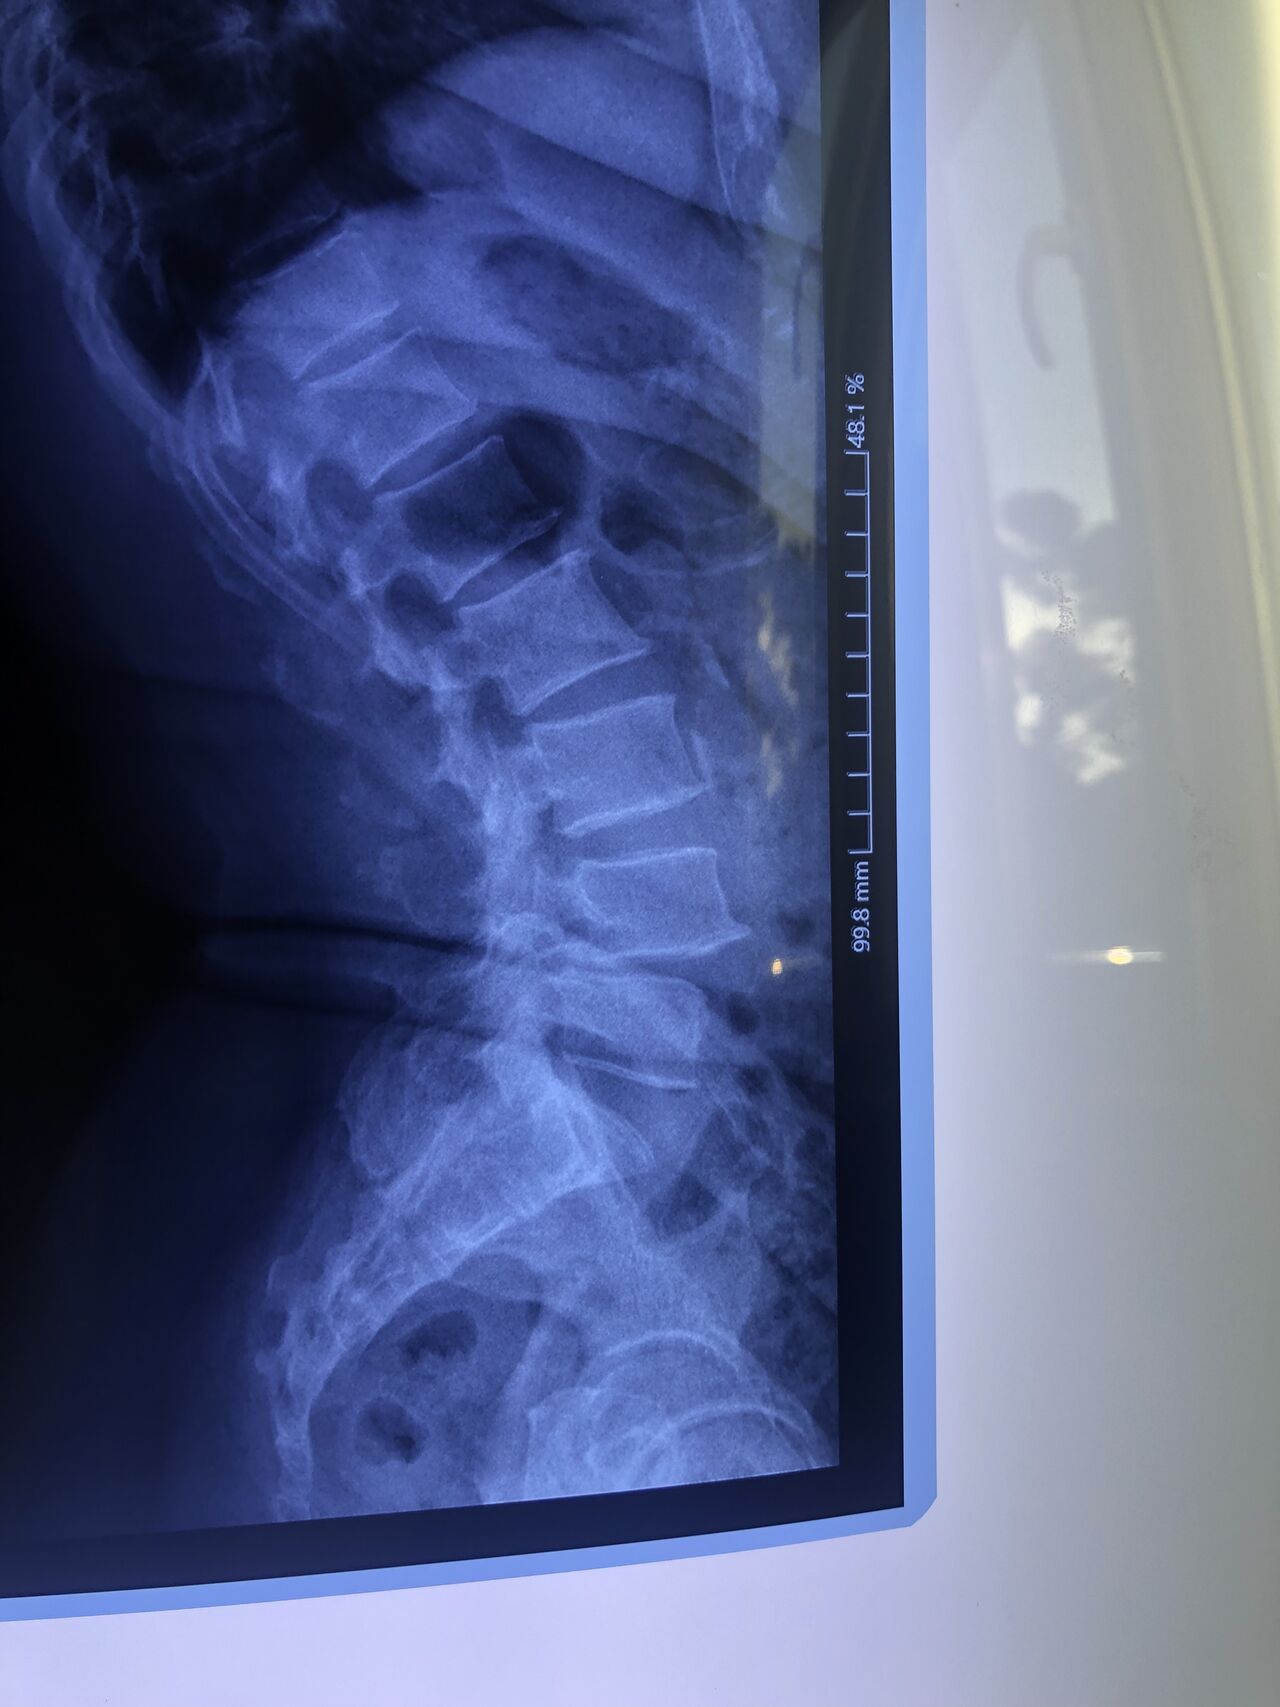

Since I’ve noticed instability in some segments I asked for dynamic L/S x ray:we see mild L4 ant listens due to DjD/DDD. There is not any pars defect.

This time presented to my cl with LBP mainly during sleep at night. Just brought me her mri. According to her mri I ordered dynamic L/S X. R.

Is ant listhesis of L4 unstable or stable?

From several compression fractures we see which of is acute/ subacute and which ones are chronic fx?